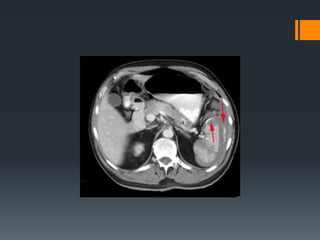

Liver Trauma

Bile duct injury